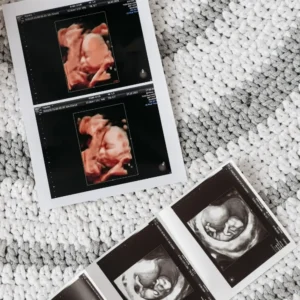

3D/4D Sonography at Shree Shreeji Women's Hospital

At Shree Shreeji Women’s Hospital, we offer advanced 3D and 4D sonography services designed to provide highly detailed, accurate imaging for comprehensive pregnancy care and women’s health. Using state-of-the-art ultrasound technology, our specialists deliver clear, high-resolution 3D images of your baby, while 4D sonography adds real-time motion, allowing parents to see the baby’s movements and facial expressions as they happen.

These innovative imaging techniques not only enhance diagnostic precision and ensure safe pregnancies but also create a joyful and emotional bonding experience for expecting parents, making every scan a memorable moment.